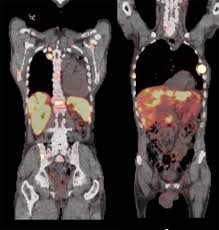

여기에 방사성 핵종 F-18를 붙여(F-18 FDG라고 함) 혈관 주사하면 빨리 자리는 암세포는 포도당이 더 필요해 정상 세포보다 10∼100배 더 많이 모여들고 이를 방사능으로 촬영해 찾아낸다. 암이 1㎝만 돼도 10조개의 암세포가 있어 CT, MRI 소견이 애매한 경우 유용하게 쓰인다.

물론 PET도 아주 작은 암은 놓치기도 하지만 대체로 약 0.5㎝ 이상의 암은 거의 80% 찾아내고 있다고 한다.

PET의 또 다른 장점으로 거의 모든 종류의 암을 찾아낼 수 있다는 것이라고 한다. 일반적으로 암세포는 포도당 대사가 높기 때문이라고 한다.

또 머리끝에서 발끝까지 촬영해 어느 곳에 있는 암이라도 잡아낸다. 다시 말하면 사각지대가 없다고나 할까? 이미 일본에서는 이 방법으로 암을 검진하는 프로젝트를 성황리에 진행하고 있다고 한다.